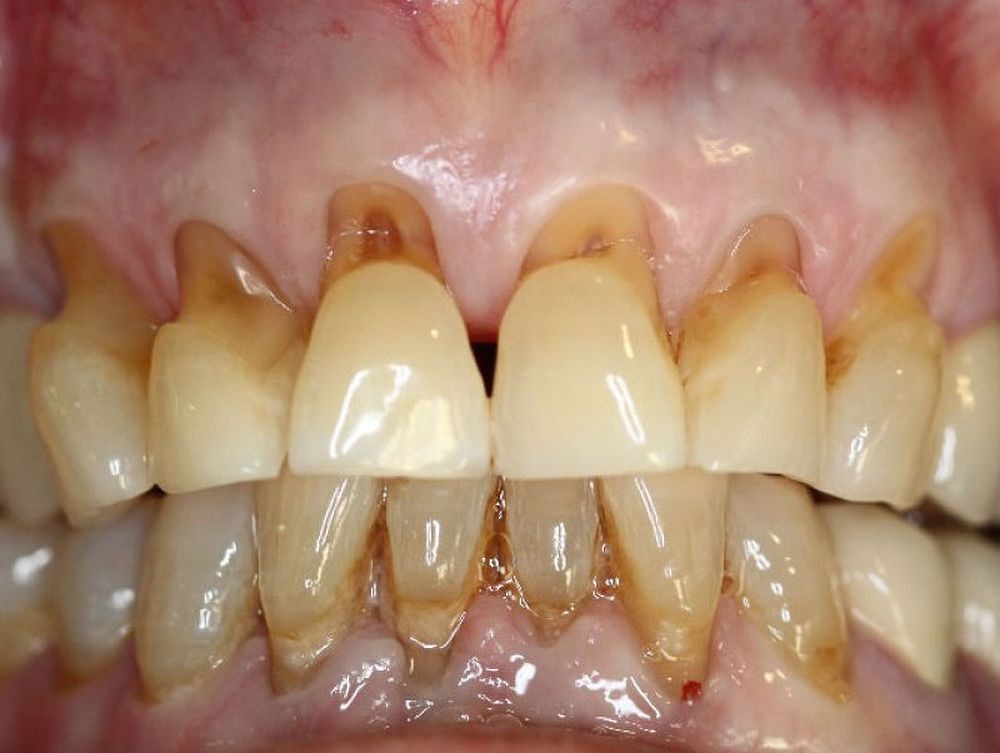

There are a couple of different ways to determine whether or not you have a dental abrasion on one or more of your teeth. The way that many dentists check for dental abrasions is by holding a light up to the teeth. Because enamel is translucent, light can be seen through it. The way that individuals can check for dental abrasion on their own is by examining their teeth and looking for any signs of V-shapes on the teeth that can indicate excessive pressure during brushing. Abrasions are visible on the cervical necks of the teeth, and they look like deep ridges. Instead of having the carious appearance that enamel usually has, it will have a shiny appearance, which indicates that some of the dentin is exposed. In some severe cases of dental abrasion, sometimes the ridge is even deep enough to see the pulp of the tooth itself.